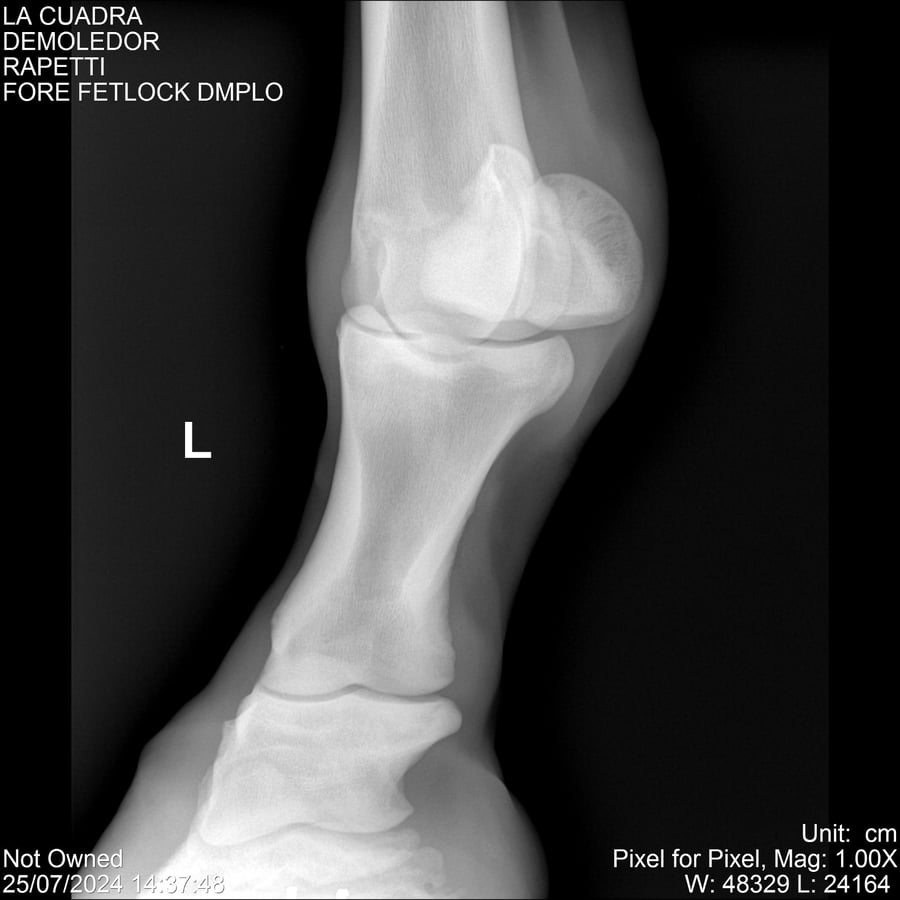

LOTE 14, DEMOLEDOR 🔥 🔥 🔥 Lote Anterior Volver al remate Lote Siguiente Ficha Contacto Montevideo - Ficha del Lote Identificador: #284454 Categoría: Yeguarizos Montevideo - 89 Visualizaciones ClicData Contacto Empresa: Abelenda N. R., Walter Hugo Nombre*: Teléfono* : E-mail* : Mensaje Enviar Registrese gratis Este contenido Exclusivo está disponible sólo para usuarios registrados Ingresar